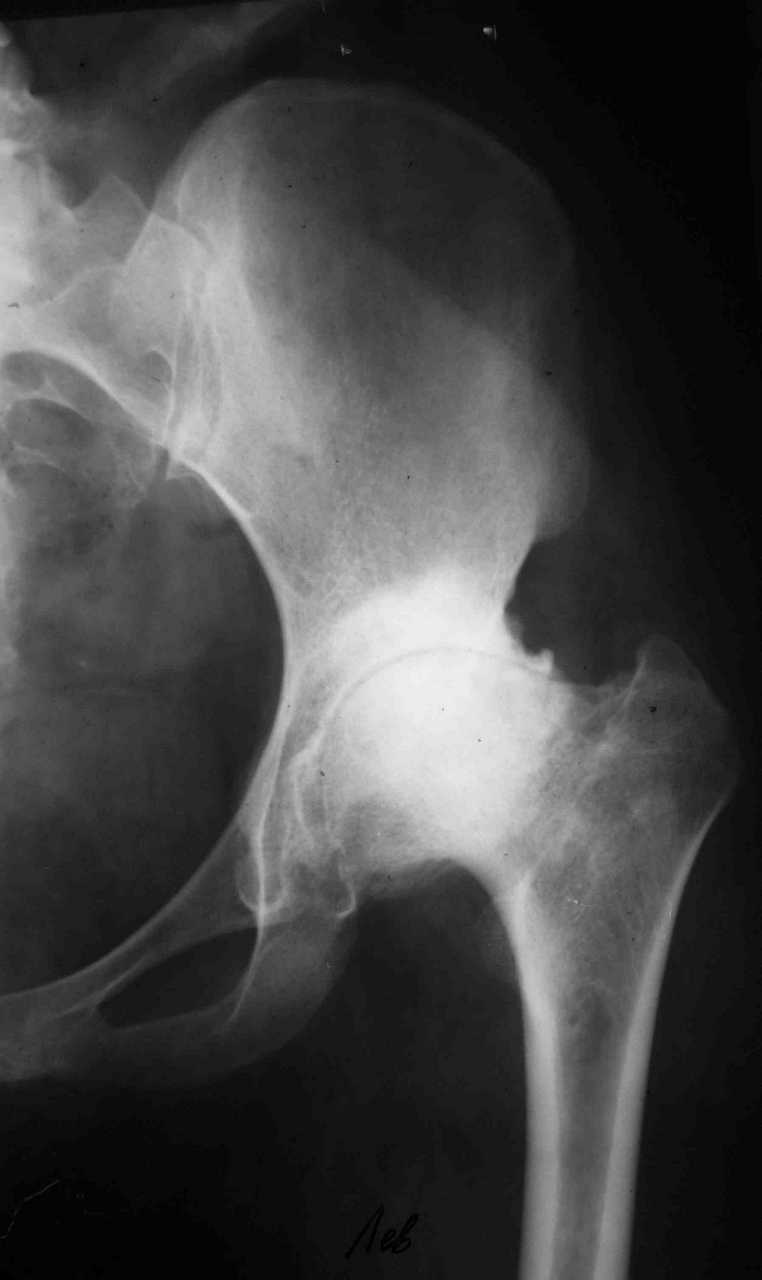

В настоящее время нет возможности сделать осевые снимки всей конечности. Это всё чем я раполагаю на сегодняшний день.

Спасибо. Картина несколько прояснилась. А планов в отношении тазобедренного сустава нет? Или пациентку беспокоит только колено.